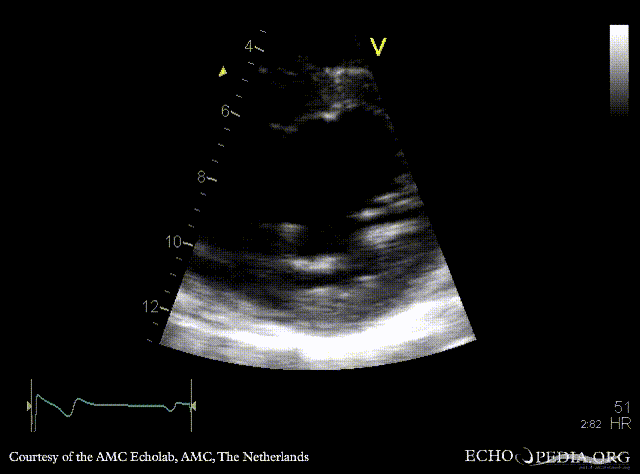

Bicuspid aortic valve

PLAX: dilated ascending aorta in patient with bicuspid aortic valve PSAX: bicuspid aortic valve